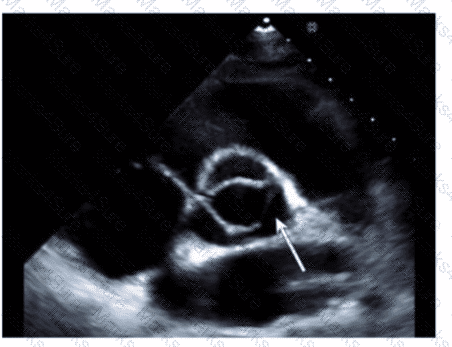

A patient presents in the emergency room with a history of chronic high Wood pressure and new onset severe back pain. A physical exam reveals a new diastolic murmur. Which would be the most likely finding?